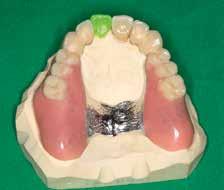

Prothetische Rehabilitation nach Resektion

Der Patient wurde im Zuge der Tumornachsorge wieder an der Universitätszahnklinik Wien vorstellig. Am Beginn der prothetischen Fallplanung wurden montierte Situationsmodelle erstellt und ein aktueller Röntgenstatus erhoben. Intraoral bestätigte sich, dass der resezierte Bereich mittels eines Zungentransplantates gedeckt wurde.

Da der Patient bereits bestehende alte

Modellgussprothesen für den Oberkiefer und den Unterkiefer hatte, wurden diese herangezogen und als Immediatersatz erweitert sowie unterfüttert. Während der Planung entschied sich das behandelnde Ärzt:innen-Team sowohl im Ober- als auch Unterkiefer für eine teleskopierende Metallgerüstprothese. Zahn 11 wurde mittels Adhäsivtechnik aufgebaut und darüber hinaus für Zahn 21 eine Einzelzahnzirkonkrone geplant. Um eine adäquate Retention der Kronen gewährleisten zu können, wurden an fünf Zähnen gegossene Stiftaufbauten eingegliedert (Abb. 6 u. 7).

Nach erfolgter Meisterabformung beider Kiefer erfolgte eine Überabformung der angefertigten Transferkäppchen mit einem individuell angefertigten Abformlöffel. Somit konnte dem zahntechnischen Labor eine präzise Schleimhautabformung zur Verfügung gestellt werden. Insbesondere wurde dabei auf die Detailtreue des resezierten Bereiches im Unterkiefer geachtet.

Anschließend an die Bissnahme mittels Bissschablonen und die gemeinsame Begutachtung der

Wachsaufstellung (Abb. 8–10) erhielt das zahntechnische Labor die Freigabe zur Erstellung der Primärund Sekundärteleskope mit Gerüsten. Diese wurden insbesondere auf ihre Passgenauigkeit und Schaukelfreiheit im Kiefer überprüft. Des Weiteren wurde bei der Erstellung auf eine Unterspülbarkeit des transplantierten Gebietes geachtet. Nach erfolgter Wachsaufstellung auf Gerüst wurde die Fertigstellung der Teleskopprothesen und der Einzelzahnzirkonkrone in

Auftrag gegeben. Für Zahn 11 wurde vom zahntechnischen Labor ein entsprechendes Mock-up mit Schiene zur Übertragung erstellt (Abb. 11–23). Anschließend an die komplikationslose Eingliederung der Arbeit erfolgte eine Kontrolle sieben Tage nach erfolgter Übergabe (Abb. 24, Seite 7). Nach der Durchführung von minimalen Korrekturen an der Okklusion wurde der Patient in den Recall entlassen.•

Abb. 11: Fertigstellung Abb. 12: Fertigstellung Abb. 13: Fertigstellung Abb. 14: Fertigstellung Abb. 16: Fertigstellung Abb. 15: Fertigstellung